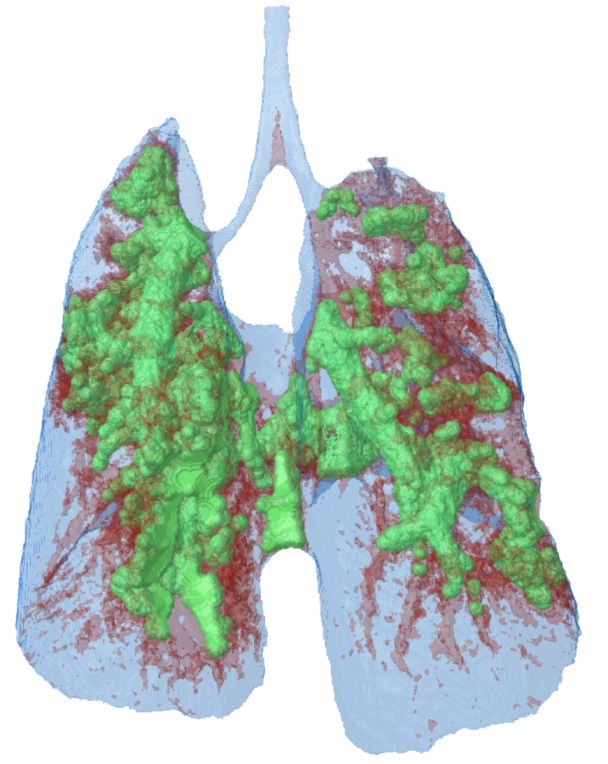

10. 3D model of a mouse lung, made transparent to visualize thelung tumour tissue in green.

14.png